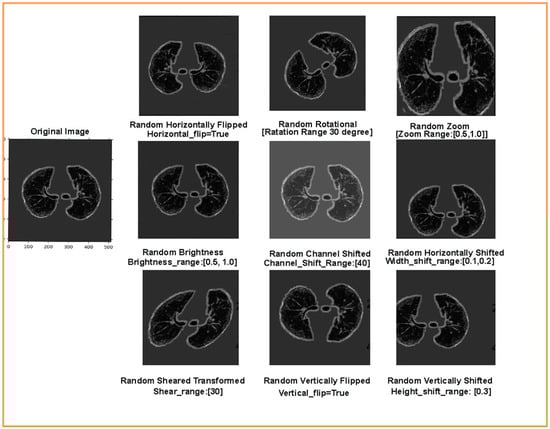

• Due to a limited dataset for each class, a novel augmentation queues method was used to generate more similar images for each category. In addition, to enhance the training data, various transformation strategies, such as flipping, shifting, rotation, zoom, shear transformation, channel shift, and brightness, were used under a specific range.

However, implicit regularization is employed during the training without confining the capabilities of the DNN model. Implicit regularization is of two types: early stopping and data augmentation. Early stopping is the end of the training process whensoever there is an increase in the generalization error (difference between the training and the validation error). We used early stopping to avoid overfitting because of a vast data load in the step per epoch. Data augmentation generates new training sample data from the original by employing image transformations using various artificial image synthesis methods. In the present study, to perform the binary classification of the input chest CT images, the pre-trained transfer learning models are retrained by updating fully connected layers according to the input-labeled masked image data. Pre-trained deep CNN models require a large amount of labeled training image data, which enables the deep CNN models to learn all the details and variations in the images for improved learning performances and enhanced generalization. Augmentation is applied to an image dataset to increase the size of the dataset by artificially generating variation in the input image data. Using data augmentation during training, the DNN is trained and validated on continuously changing versions of the input-masked images, allowing the DNN to have effective learning and more robust features [41]. Note that the labels of the augmented images will be the same as those of the original input mask images. In this study, we have applied a novel Augmented Queue method [42] to yield images on-the-fly during deep CNN model training and validation. The augmented queue method addresses the dual problem (limited data and class imbalance) by performing on-the-fly data augmentation, a multi-queue memory to keep separate and balanced queues for each class, and active online learning. Thus, to enhance the training and validation of image data, augmentation operations such as flipping, rotation, shifting, zoom, shear transformation, channel shift, and brightness were performed under a specific range, as shown in Figure 8.

Figure 8. Augmented training and validation data after flipping, rotation, shifting, zoom, shear transformation, channel shift, and brightness operations.